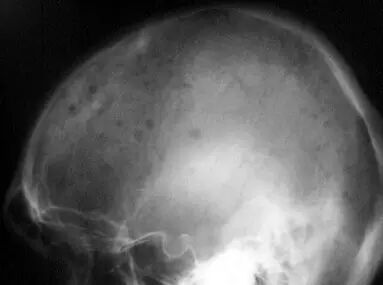

1.1 多发性骨髓瘤的头骨

骨髓瘤细胞在骨髓中增生,刺激由基质细胞衍变而来的成骨细胞过度表达 IL-6,激活破骨细胞,导致骨质疏松及溶骨性破坏。骨痛为常见症状,随病情发展而加重。